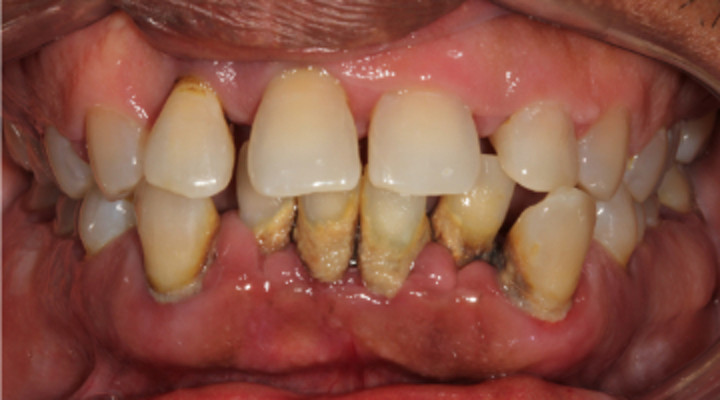

Black Teeth: Symptoms, Causes and Treatment

Black teeth can be a concern for many people; a black tooth will affect your smile and impact on your confidence. If you have a black tooth, read on to find out more about the symptoms and causes and treatments that may be available.

What causes a tooth to go black?

There are many reasons why a tooth can begin to go black, anything from simple staining to the death of the tooth can cause blackness and darkening.

Poor oral hygiene

Poor oral hygiene can cause your tooth to go black. In the early stages this is likely to be staining from substances like tobacco, red wine and strongly colored food. If your oral hygiene routine is not thorough enough to remove the acid-excreting bacteria each day, the acid will slowly eat away at your tooth.

As the tooth gets eaten away, tooth decay sets in. Tooth decay naturally looks black and can give the appearance of a black tooth. This gives the look of rotten teeth and is a classic result of not looking after your teeth for a considerable period of time.

The death of a tooth

When a tooth dies, the blood supply – which gives the tooth its natural, healthy color – will stop. Because the tooth is not receiving the nutrients it needs, it will begin to necrotise, darken, die and slowly go black.